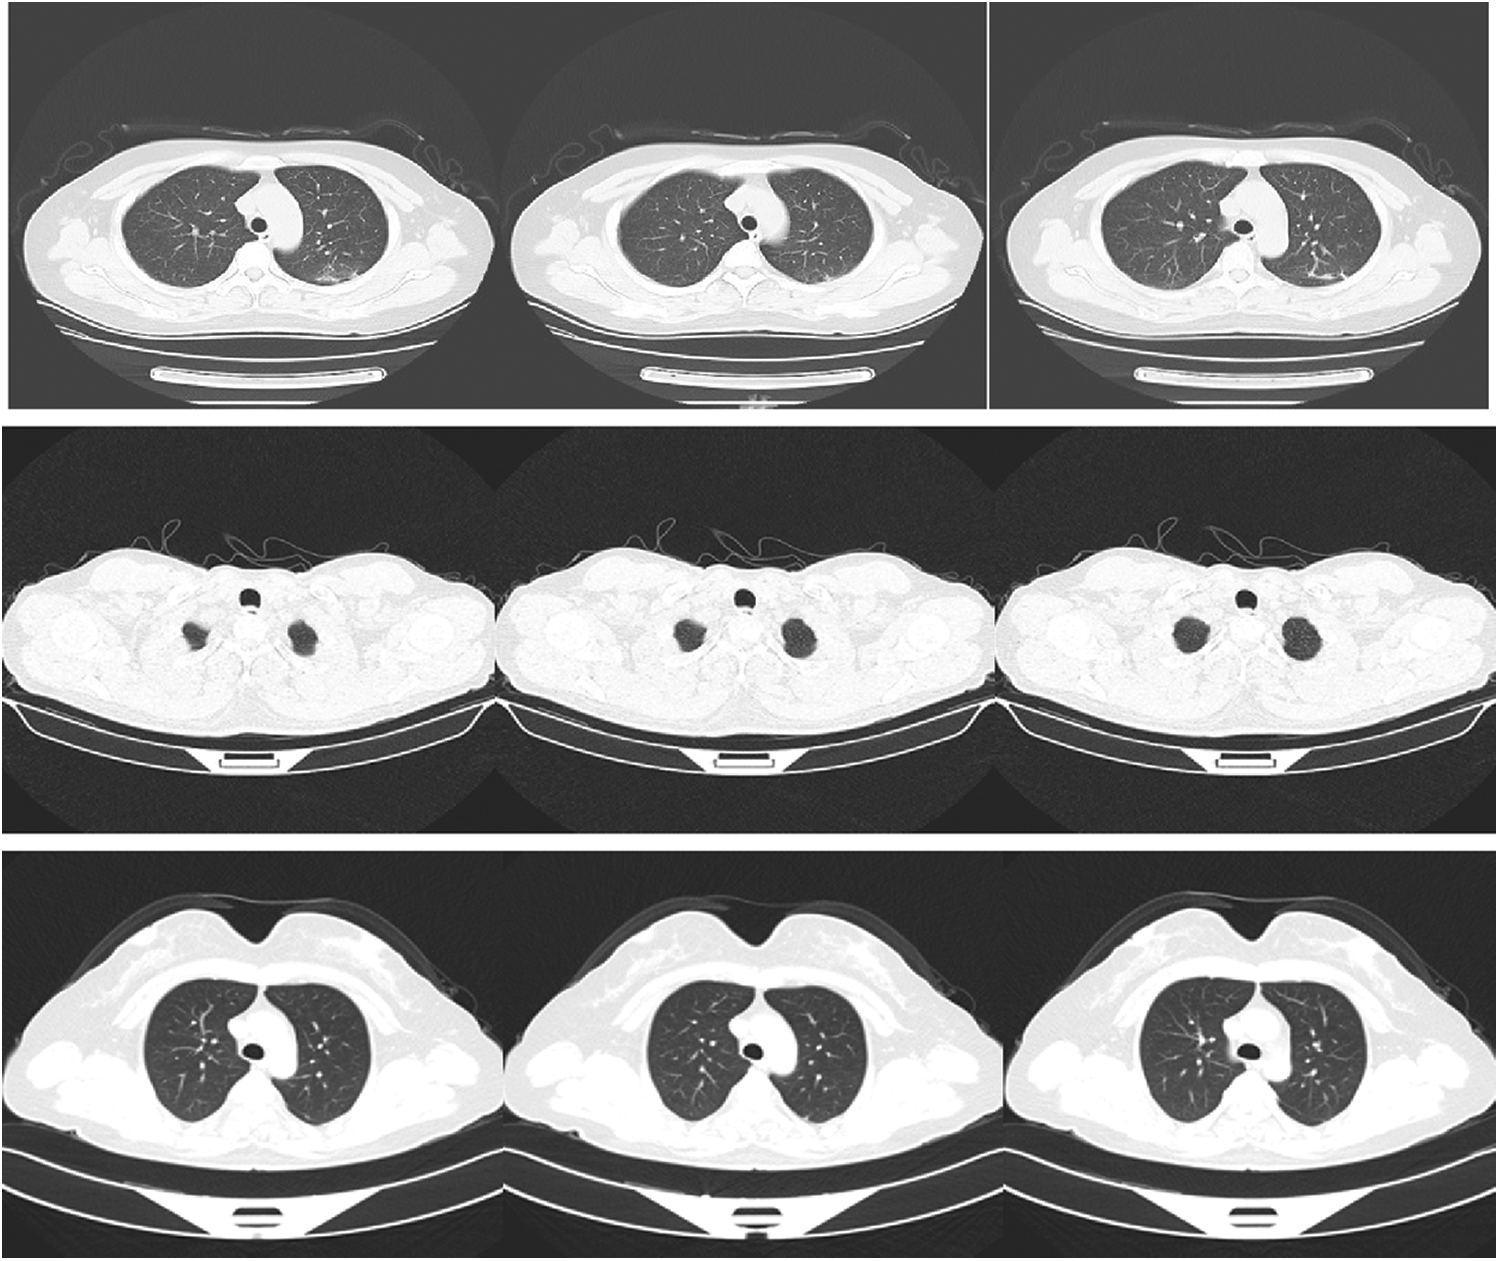

The used dataset contains CT images for normal, pneumonia, and COVID-19 cases. This dataset has been acquired by China national center of bio-information. The size of the input images is 512 × 512. The images were downloaded from Kaggle repository. Fig. 2 shows sample images of normal, pneumonia, and COVID-19 cases.

Figure 2: Samples of images of COVID-19, pneumonia, and normal cases